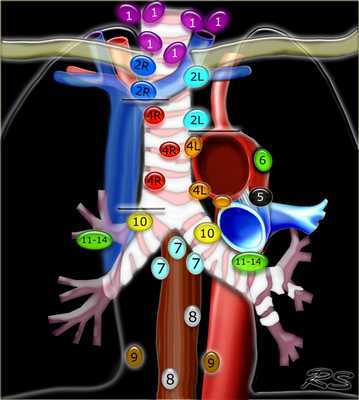

Лимфатические узлы средостения

Лимфатические узлы 3 группы не примыкают к трахее в отличии от лимфатических узлов 2 группы. Они подразделюятся на: 3А кпереди от сосудов 3Р позади пищевода/превертебрально Они не доступны при медиастиноскопии. 3Р группа может быть доступна при чреспищеводной эхокардиографии.

На изображении слева 3А узел в преваскулярном пространстве. Обратите внимание так же на ниже расположенные паратрахеальные узлы справа относящиеся к 4R группе.

4R. Правые нижние паратрахеальные лимфатические узлы

- Верхняя граница: пересечение нижнего края левой плечеголовной вены с трахеей.

- Нижняя граница: нижний края непарной вены. 4R узлы распространяются до левого края трахеи.

На изображении слева мы видим 4R паратрахеальные узлы. Кроме того здесь представлен узел кнаружи от дуги аорты, то есть 6 группы.

4L. Левые нижние паратрахеальные лимфатические узлы

4L узлы расположенные слева от левой стенки трахеи, между горизонтальными линиями проведенными касательно верхней стенке дуги аорты и линией проходящей через левый главный бронх на уровне верхнего края верхнедолевого бронха. Они включают паратрахеальные узлы расположенные кнутри от артериальной связки.

Узлы 5 группы (аортопульмонального окна) расположены кнаружи от артериальной связки.

На левом изображении над уровнем легочного ствола представлены нижние паратрахеальные узлы слева и справа, так же здесь представлены узлы 3 и 5 групп.

Изображение слева выше уровня карины. Слева от трахеи 4L узлы. Обратите внимание что они расположены между легочным стволом и аортой, но не в аортопульмональном окне, потому что они лежат медиальнее артериальной связки. Лимфатические узлы латеральнее легочного ствола относятся к 5 группе.

- 5. Субаортальные лимфатические узлы

- Субаортальное или аортопульмональное окно расположено кнаружи от артериальной связки и проксимальнее первой ветви левой легочной артерии и лежит в пределах медиастинальной плевры.

- Парааортальные лимфатические узлы лежат кпереди и кнаружи от восходящего отдела аорты и между верхним и нижним краями дуги аорты.

1. лимфатические узлы вырезки грудины видны только на этом уровне и выше него

2. верхние паратрахеальные лимфатические узлы: ниже ключиц , справа над пересечением нижнего края левого плечеголовного ствола и трахеи, а слева над дугой аорты

3. Преваскулярные и ретротрахеальные: кпереди от сосудов (3А) и превертебральные (3Р)

4. Нижние паратрахеальные: ниже верхнего края дуги аорты до уровня главного бронха

5. Субаортальные (аортопульмональное окно): лимфатические узлы кнаружи от артериальной связки или кнаружи от аорты или левой легочной артерии.

6. Парааортальные: узлы лежащие кпереди и кнаружи от восходящего отдела аорты и дуги аорты под верхним краем дуги аорты.

7. Субкаринальные лимфатические узлы.

8. Параэзофагеальные лимфатические узлы (ниже карины).

9. Лимфатические узлы легочной связки: лежат в пределах легочной связки.